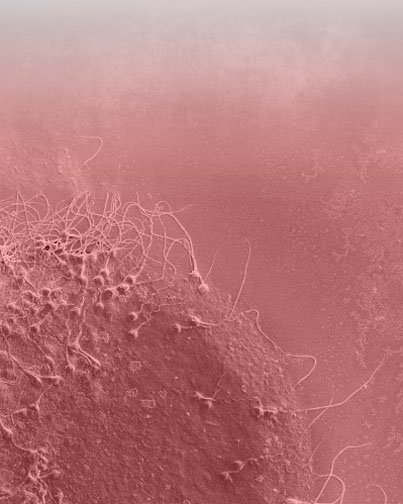

Pourquoi l’étude de l’embryon avec le PGS/PGT-A/CCS peut nous aider à remporter la grossesse?